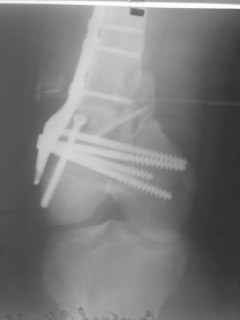

01.12.09г. оперировал больного с подобной травмой в ЦРБ на 4-е сутки после ДТП. Перелом открытый - рана находилась медиально чуть выше надколенника длиной примерно 3-4 см. До этого при поступлении было выполнено ПХО раны и скелетное вытяжение. На момент операции рана без признаков воспаления, состояние больного удовлетворительное.На первичных снимках перелом А3. На операции оказалось С3. Перелом фиксирован мыщелковой пластиной. Для репозиции понадобился медиальный доступ. Медиальный блок дополнен костно-губчатым аутотрансплантатом. На сегодняшний день раны заживают первично, швы еще не сняты, температура тела нормальная, отек бедра значительно уменьшился, имеется анемия средней степени, проводится ЛФК. Фото досылаю